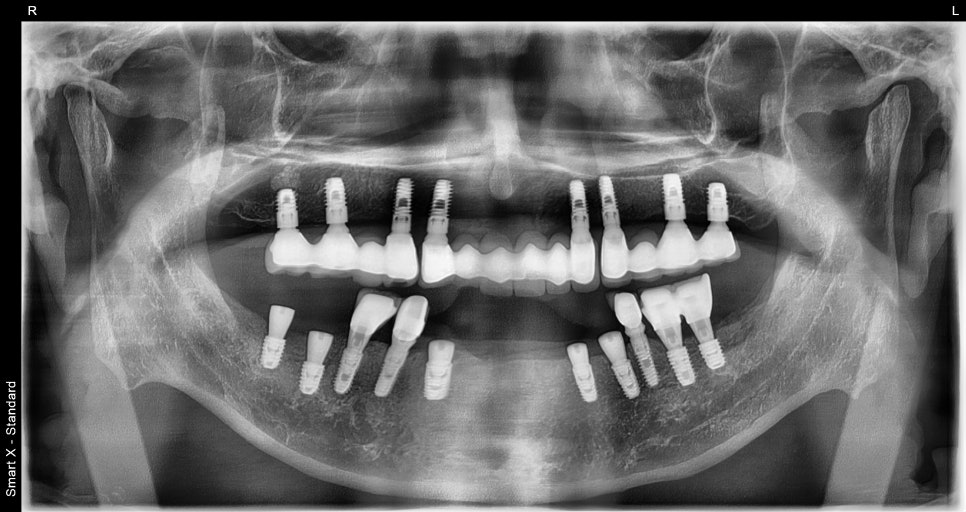

왼쪽 사진: 치료 전 전체 엑스레이입니다. 아래쪽엔 파절된 임플란트가, 위쪽엔 기존 임플란트 보철 상태가 보입니다.

치료 전: 아랫니 앞니 흔들림 & 보철 빠짐, 왼쪽 아래 파절된 임플란트